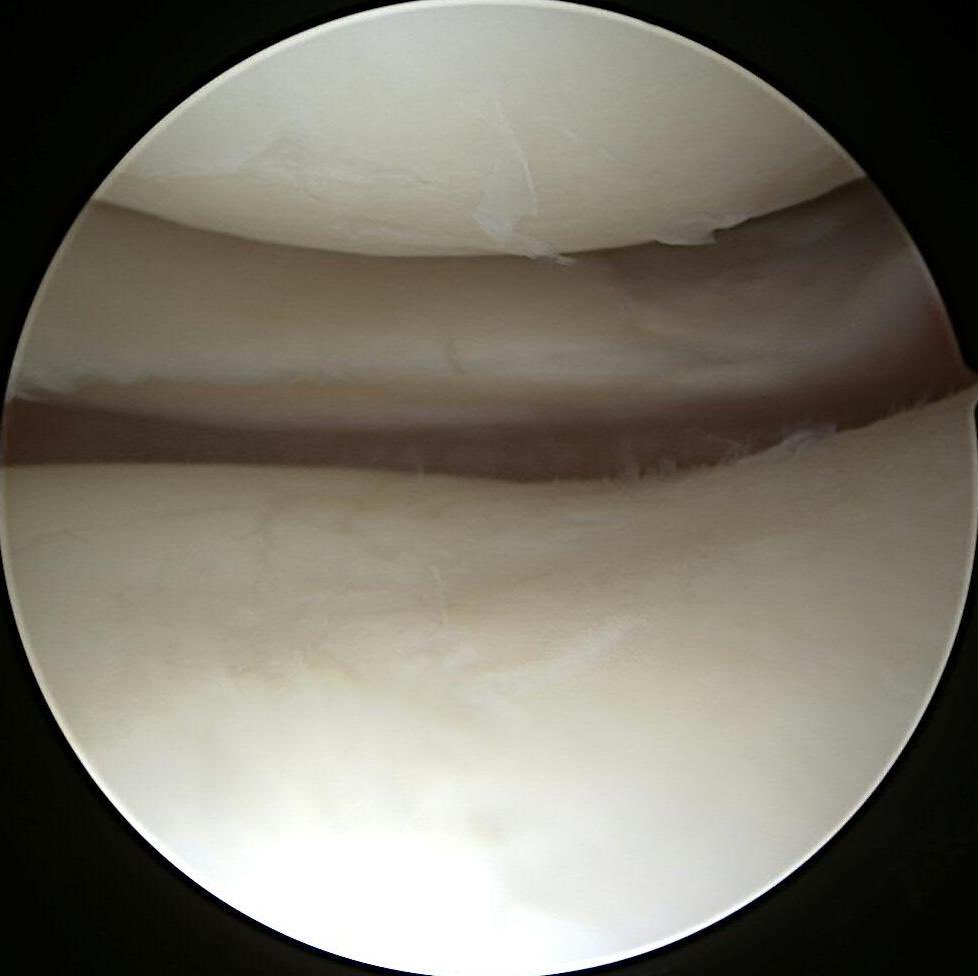

Hot off the press in #JAAOS - Our review and preferred management of meniscus root tears with Dr. Aaron J. Krych Devin Leland and Michael J. Stuart. Safe and efficacious, with proven patient quality of life and societal cost benefits. #SaveTheMeniscus ncbi.nlm.nih.gov/m/pubmed/31693…